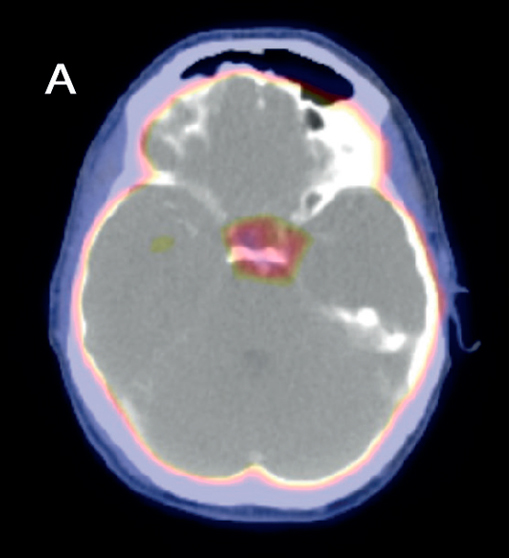

En el seguimiento, se solicitó una tomografía por emisión de positrones (PET-CT) en búsqueda de lesiones en otras regiones corporales. Se evidenció un aumento de captación en sector lateral izquierdo en región selar sin correlato morfológico, lo que es inespecifico. No se evidencian lesiones en pulmones ni en estructuras óseas (Figura 3). Se plantea que el paciente está en remisión, y se continuará su seguimiento.